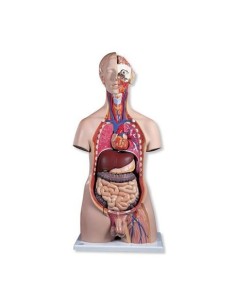

3B Scientific, Torse bisexuel, modèle de luxe, séparable en 20 parties B32

3B Scientific, Torse bisexuel, modèle de luxe, séparable en 20 parties B32